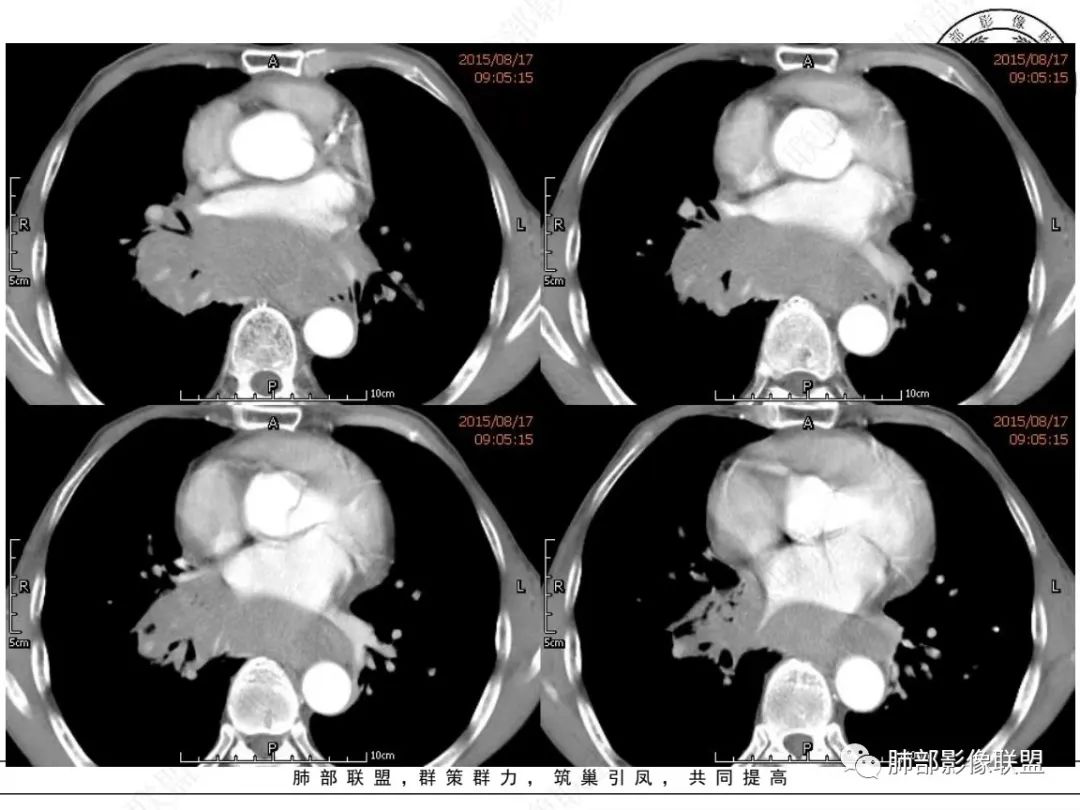

放射小白:老年男性,右侧肺门可见团块状占位包绕气管,气管受压变窄,纵隔见巨大团块状占位,另纵隔可见肿大淋巴结,增强肺门及纵隔肿块强化不明显,内部可见血管影,周围结构只是受压移位,另颌下淋巴结穿刺慢性淋巴结炎,首先考虑小细胞癌,鉴别淋巴瘤、结节病。

宇宙:右肺下叶小结节,右肺门及中后纵膈淋巴结肿大融合,强化均匀,主支气管、中间段及下叶支气管受压变窄,右下肺静脉受压变窄,考虑小细胞癌,鉴别淋巴瘤

丽:老年男性,纵隔及肺门多发肿大淋巴结,相互融合呈团块状,包绕支气管官腔,呈针尖样狭窄,增强后轻度强化,考虑小细胞肺癌

放射线:纵隔及肺门淋巴结肿大相互融合呈冰冻纵膈,支气管受压变窄呈针孔样,老年男性吸烟患者,考虑小细胞肺癌。

采莲:老年男性,有吸烟史,双颈部肿块,双肺纵隔淋巴结多发淋巴结肿大并融合成块,气管及右肺下叶支气管受压狭窄,考虑恶性,淋巴瘤可能,鉴别小细胞肺癌。

崔少钢:老年男性,有吸烟史,右肺下叶背段示小结节,纵隔、腋窝及右肺门淋巴结节肿大,气管受压狭窄,后纵隔软组织内示血管走行,考虑小细胞>淋巴瘤。

我只是邓较瘦:晨读老年男性,长期吸烟。右肺门、纵隔多发肿大淋巴结、融合成团块,中间支气管、右肺下叶支气管受压变窄,增强扫描强化程度较轻,血管包埋。另两侧腋窝亦见多发肿大淋巴结。常规恶性没问题,小细胞?淋巴瘤?但是於老师的病例总感觉没那么简单。

谢加平:纵隔内中后纵隔及右肺门淋巴结肿大,形成大肿块,整体密度均匀,并轻度强化,见“血管飘浮”征,包绕气管分叉及右主支气管及中间段支气管明显受压狭窄,并包埋右肺门血管束,无侵蚀破坏,右肺动脉后壁见压迹影,右肺下叶背段有阻塞性炎症,首选淋巴瘤,支气管超声内镜活检,明确诊断!